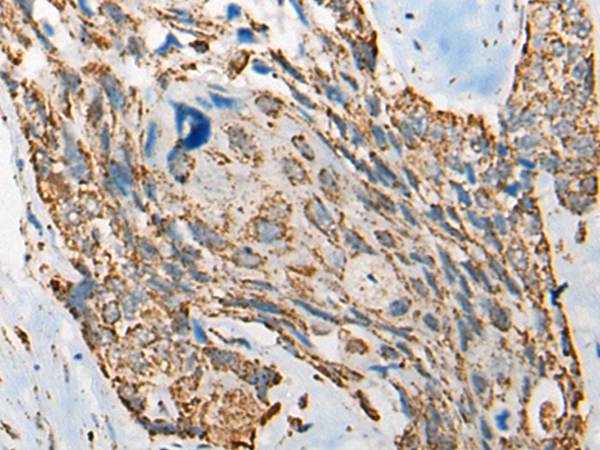

分类: 科研抗体货号: P09467别名: SORORIN应用: IHC反应种属: Human